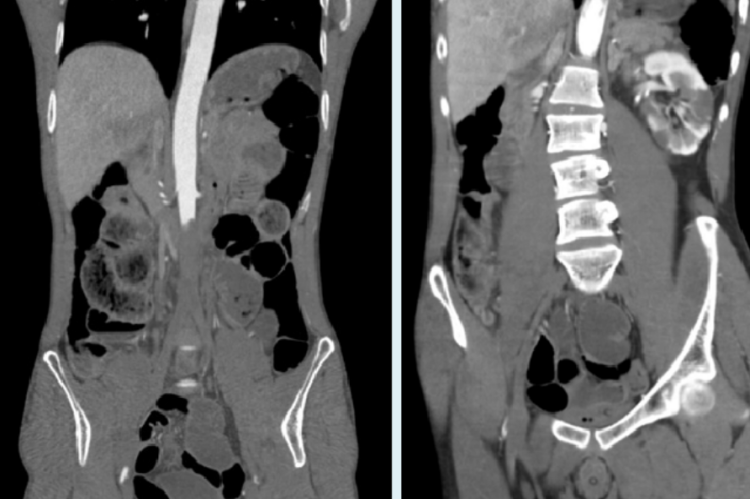

CT Angiography scan uses

A CT angiography scan is carried out to check for any abnormality in the blood vessels of the brain, lungs, heart, kidneys, or any other part of the body. It helps diagnose the cause of chest pain or other related symptoms. A CTA scan shows more detailed images of inside the head, neck, abdomen, and other parts of the body and can be used during surgery to look at the blood vessels which are being repaired.

● Tumors